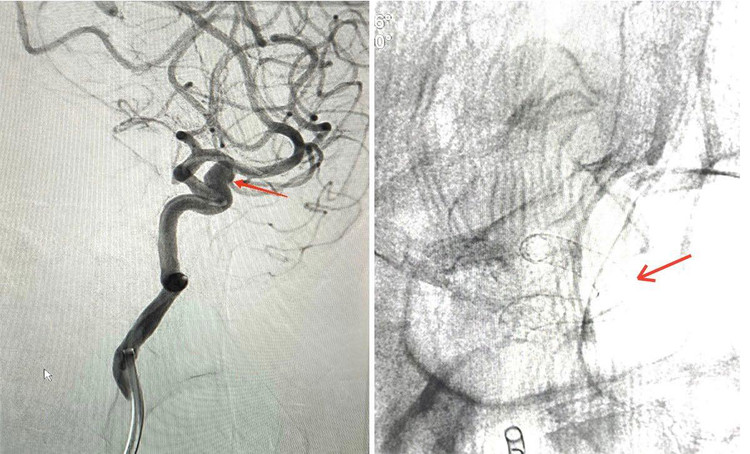

| Ca can thiệp đặt stent mạch não chuyển dùng được các bác sĩ Trung tâm Đột quỵ Bệnh viện Đa khoa tỉnh Phú Thọ thực hiện - Ảnh BVCC |

Chị N.T.H (46 tuổi) ở Phù Yên – Sơn La, với triệu chứng thường xuyên bị đau đầu kèm với buồn nôn. Chị đã đến Bệnh viện đa khoa tỉnh Phú Thọ thăm khám, được các bác sĩ chỉ định chụp cộng hưởng từ 3.0T mạch não, kết quả phát hiện chị H bị phình cổ rộng động mạch cảnh trong hai bên đoạn xoang hang.

Động mạch cảnh bên trái có nguy cơ vỡ cao hơn nên đã được các bác sĩ trong ekip đặt stent chuyển dòng trước, động mạch cảnh bên phải sẽ làm trong thì sau. Kích thước túi phình 4,5mm x 5,5mm cổ túi 4mm. Đây là nguyên nhân gây ra những cơn đau đầu dai dẳng mà chị H phải chịu đựng.

Với trường hợp của người bệnh H, sau khi được phát hiện khối phình mạch não, người bệnh được hội chẩn bởi các bác sỹ có chuyên môn cao trong lĩnh vực can thiệp mạch máu não thuộc Trung tâm Đột quỵ – Bệnh viện Đa khoa tỉnh Phú Thọ và được chỉ định đặt stent chuyển hướng dòng chảy điều trị túi phình.

Sau khi được tư vấn phình mạch não sẽ vỡ bất kỳ khi nào và mức độ nguy hiểm khi túi phình vỡ sẽ để lại các di chứng rất nặng nề, thậm chí tử vong. Người bệnh đã được các Bác sĩ của Trung tâm đột quỵ thực hiện can thiệp đặt stent chuyển dòng mạch não, thời gian can thiệp chỉ khoảng 2 giờ. Ngay sau khi đặt xong stent, dòng máu đi vào trong lòng túi phình giảm hẳn, đã được kiểm soát và nguy cơ vỡ túi phình cũng giảm theo